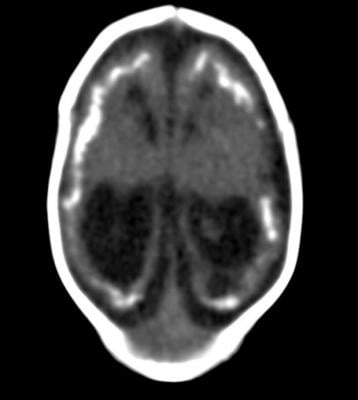

Advances in neuroimaging have provided opportunities to explore the role of hippocampal calcifications in dementia. The development of multiplanar brain computed tomography (CT) scans has enabled better distinction between hippocampal calcifications and calcifications in nearby brain structures like the choroid plexus.

“A multiplanar CT scan makes it possible to see the hippocampus in different anatomical planes; for example, from top to bottom, right to left, and front to back,” de Brouwer said. “Before multiplanar CT scans, hippocampal calcifications were often mistaken for choroid plexus calcifications. So with multiplanar CT scans, hippocampal calcifications are better distinguished from calcifications in other areas.”

The study group included 1,991 patients, average age 78 years, who had visited a memory clinic at a Dutch hospital between 2009 and 2015. The patients had a standard diagnostic workup including cognitive tests and brain CT scans. The researchers analyzed the CT scans for the presence and severity of hippocampal calcifications.

Of the 1,991 patients, 380 (19.1 percent) had hippocampal calcifications. Older age, diabetes and smoking were associated with an increased risk of hippocampal calcifications on CT scans.